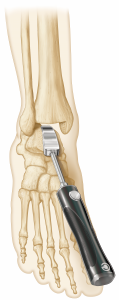

(Figure 5) The instrumentation to prepare the tibia for vertical peg and cage orientation is unique and simple to use (Figure 6); the Advita engineering team was brilliant in creating this impaction system disproving many doubters, including myself, that such an impactor could be safely introduced despite the ankle joint’s relatively limited access. The Vantage talar component’s backside has a uniform curve that optimizes compressive forces on the prepared dome-shaped talus throughout the ankle’s full range of motion. In contrast, nearly all competitors’ talar components provide alarm component stability via chamfer cuts that tend to create the potential for shear stresses. (Figure 5) One recently released total ankle system, features a uniform dome-shaped talar preparation like that of the Vantage but requires a lateral approach and fibular osteotomy for component implantation. The Vantage’ talar component confers the same talar component advantages via the far more commonly used anterior approach and does not require a fibular osteotomy. Unique to the Vantage total ankle system, a simple manual rasp is used to complete the uniform talar dome preparation.

Our ankle design team spent the better part of four years devising and perfecting the Vantage surgical technique. Our initial thoughts favored sophistication and complexity to confer advantages over the competitors’ ankles. However, complexity and its accompanying frustrations soon gave way to simplicity. The current surgical technique and instrumentation is remarkably straightforward. I recently taught a Vantage cadaver lab to a group of residents; none of the residents had prior experience performing a total ankle replacement. I can confidently state that the residents’ implanted Vantage ankles were on par with the first Vantage cadaveric ankle implantations of nearly every experienced foot and ankle surgeon at our training labs. The external tibial alignment guide is reliable in properly orienting the tibial cut, and punching the relief areas for the tibial component pegs and cage is easily learned. Talar preparation is uncomplicated, with reproducible positioning of the talar component in both the coronal and sagittal planes (Figure 9); creating the uniform talar dome arc is facilitated by the user-friendly manual rasp.